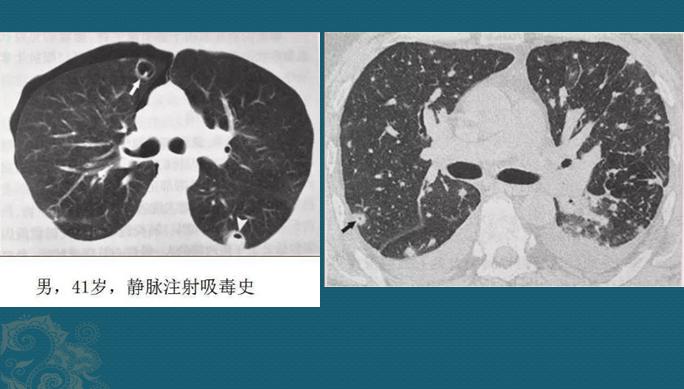

血源性的通常比较重!金葡菌一旦得势,形成局部脓肿大量繁殖,细菌入血,就像野草种子一样,随血液可以到达全身任何部位,常见的有骨髓、关节、大脑、双肺、肾脏等。

如果它们抵达肺部小血管周围生根发芽,就会制造各种毒素引发炎症,表现为多发点片状影或类圆形结节影,边缘清晰或模糊,沿支气管血管束或肺外周和基底部分布,因为是化脓性感染,多数结节最后会坏死、液化,形成空洞,当损伤血管或者形成血管内菌栓堵塞还可以引起远侧肺策划缺血坏死(肺梗死),形成胸膜下楔形肺实变影。

这些都是金葡菌小草刚发芽,多发小结节、小斑片影,有的形成了小空洞和小气囊,部分与血管关系密切,提示病菌是从血道来源引起肺部播散,及时抗生素治疗可以压制炎症发展。